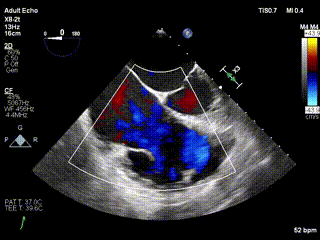

2021年12月24日,復(fù)旦大學(xué)附屬中山醫(yī)院葛均波院士團(tuán)隊(duì)成功應(yīng)用LuX-Valve Plus為一例極重度三尖瓣反流(TR)合并房顫、房缺的患者完成了經(jīng)血管三尖瓣置換術(shù),這是在前基礎(chǔ)上,本周完成的第三例經(jīng)血管三尖瓣置換手術(shù),葛均波院士、周達(dá)新教授等與心外科魏來(lái)教授、賴顥教授,心超室的潘翠珍教授、李偉教授及麻醉科的郭克芳教授共同完成了本周手術(shù),均獲得圓滿成功!患者術(shù)后超聲顯示無(wú)TR,臨床癥狀明顯改善。本周手術(shù)的成功也為L(zhǎng)uX-Valve Plus救治性臨床研究添上了濃墨重彩的一筆。

本周三例接受LuX-Valve Plus經(jīng)血管三尖瓣置換術(shù)的患者中,第一例患者為冠狀動(dòng)脈旁路移植術(shù)+Bentall+二尖瓣成形術(shù)后;第二例患者為永久起搏器植入術(shù)后,存在跨三尖瓣導(dǎo)線;第三例患者合并房顫、房缺及左心耳封堵術(shù)后。

三例患者入院后,葛均波院士團(tuán)隊(duì)周達(dá)新教授、潘文志教授、張?jiān)床┦?、陳莎莎博士及心超室的潘翠珍教授、李偉教?/strong>對(duì)患者的情況進(jìn)行詳細(xì)評(píng)估和討論,最終決定為三例患者選擇LuX-Valve Plus40mm、50mm和50mm型號(hào)的瓣膜進(jìn)行手術(shù)治療。手術(shù)后即刻拔除氣管插管,術(shù)后患者三尖瓣反流癥狀得到顯著改善,復(fù)查心超結(jié)果顯示人工三尖瓣瓣膜支架固定穩(wěn)定,瓣葉關(guān)閉形態(tài)未見(jiàn)異常,未見(jiàn)明顯反流。